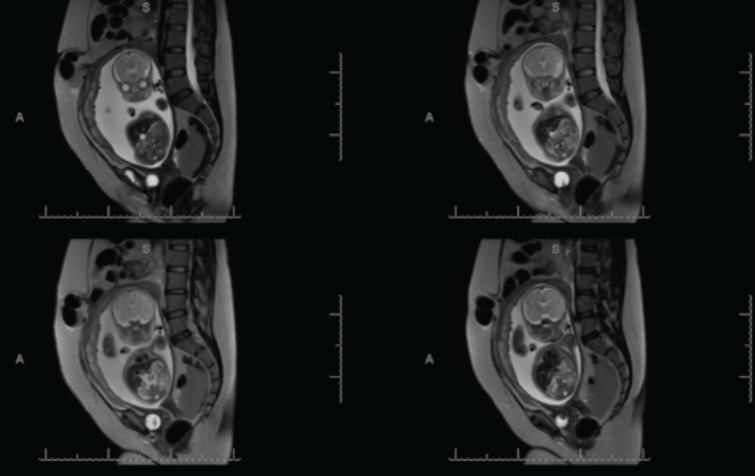

Second-trimester spontaneous uterine rupture: a rare case of diagnostic nuances and multidisciplinary management